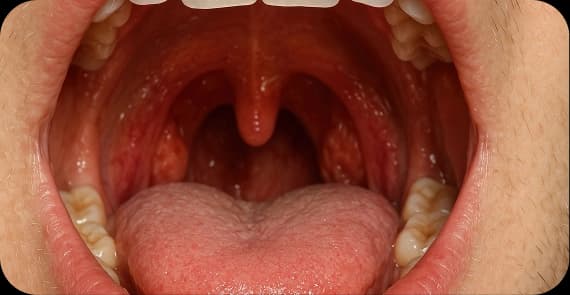

The tongue is divided into two main parts: the oral tongue, which is the front two-thirds, and the base of the tongue, which is part of the throat. What happens in tongue cancer is the transformation of normal cells into malignant cells that may invade surrounding tissues or spread to lymph nodes in the neck.

Tongue cancer symptoms can vary depending on tumour size and location.

Early-stage tongue cancer symptoms may include small, painless ulcers or patches that do not heal. Identifying early tongue cancer symptoms and seeking timely evaluations can significantly improve outcomes.